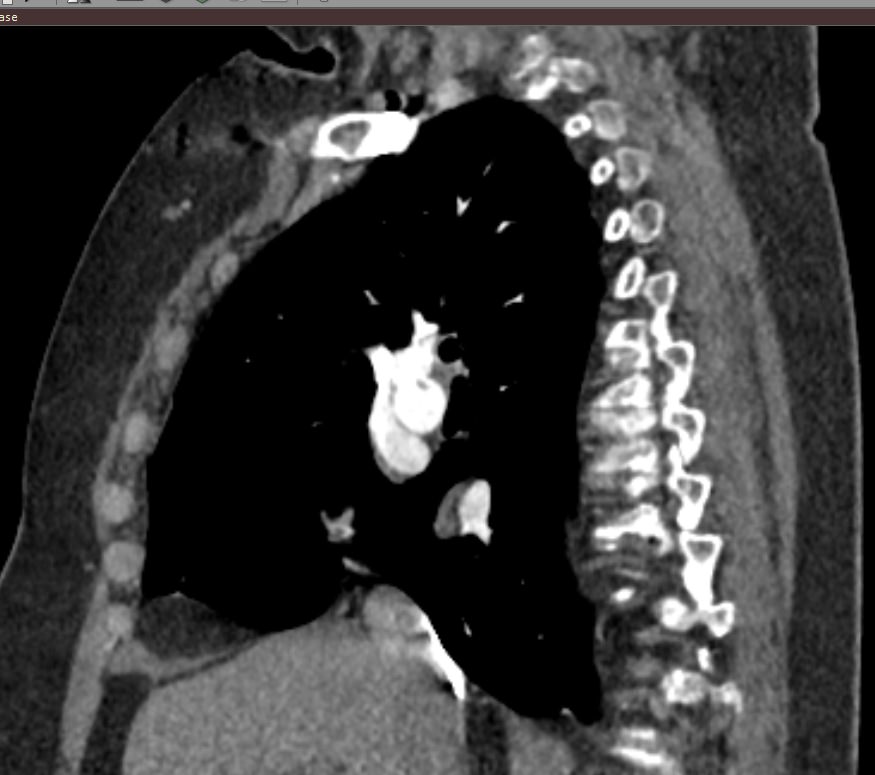

Наиболее информативным, при этом быстрым и неинвазивным (то есть без вмешательства в организм пациента), методом диагностики патологии легочной артерии является мультиспиральная компьютерная томография (КТ-ангиография). Методика основана на использовании рентгеновского излучения в сочетании с цифровой обработкой данных для получения трехмерных изображений сосудистой системы.

Для визуализации кровеносных сосудов в обязательном порядке применяется контрастное усиление. Для этого в вену пациента вводится йодсодержащий контрастный препарат, который попадая в кровоток активно поглощает рентгеновские лучи и ярко контрастирует сосудистую систему, в том числе легочной артерии, на фоне окружающих тканей. Использование контраста дает возможность визуализировать даже мелкие артерии и выявить патологию.

В наших диагностических центрах КТ-ангиография легочной артерии проводится на современных мультиспиральных компьютерных томографах экспертного уровня TOSHIBA AQUILION. Оснащение аппаратов позволяет получать детальные снимки и трехмерные изображения сосудистой системы легочной артерии, при этом применение скоростной мультисрезовой методики сканирования значительно снижает уровень лучевой нагрузки на пациента.